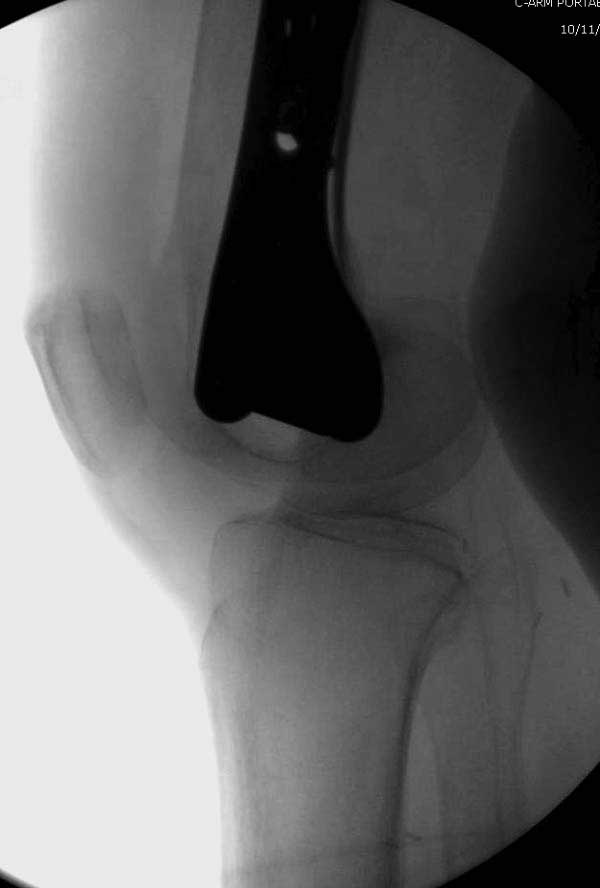

Обычно после чрезвертельных переломов, за исключением молодых, у пожилых остается нестабильность при движении. Часто падают и после 3х мес. в результате падения обнаружен перипротезный перелом (22-23), который зафиксирован Синтез пластиной.

Повторно поступает после двух с половиной лет, где обнаруживается перелом на второй стороне. Немного сложно, но для фиксации выбрали Antegrade InterTan Smith Nephew Nail и с момента фиксации более 3х мес.